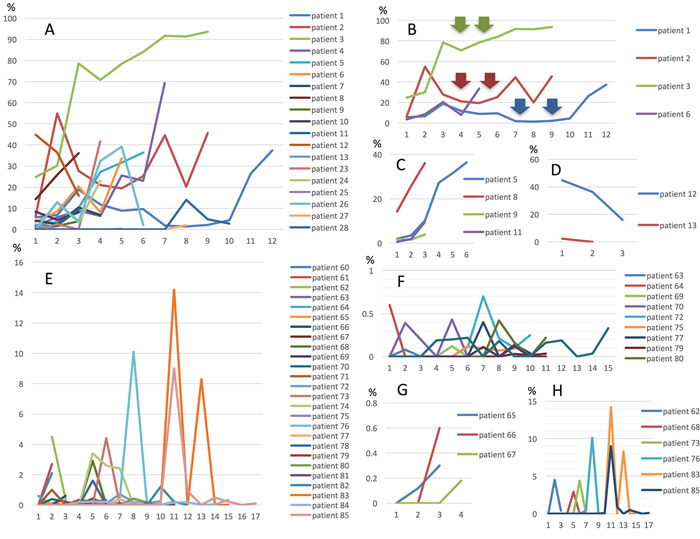

In 29 patients with the MT, MctDNA was detected in 23 patients (79.3%) (Figure 1A). Among 18 patients who underwent second-line or subsequent treatment lines, MctDNA was detected in 17 patients (94.4%). Details of the clinical course of these 29 patients is shown in Table 1. The median value of MctDNA was 64.0 copies/well (3.2–45800) for the number and 10.10% (0.26–93.60) for the ratio in these 29 patients (Figure 1B and 1C). Comparing progression-free survival (PFS) of the first-line treatment between patients with MctDNA and without, there was a significant difference in PFS (Figure 2A), with a worse outcome in patients with MctDNA (22.0 vs 3.0 months, p = 0.0007). Most patients showed a continuous change with increasing MctDNA (Figure 3A and 3C). Four patients had a stable MctDNA level, suggesting a long stable disease (Figures 3B and 4A), and two patients showed a quick decrease in MctDNA with shrinkage of tumors in response to treatment (Figure 3D and Figure 4G).

Figure 3: Changes in MctDNA during treatment in 29 patients with mutations in tumor tissues (A), representative graph of four patients with stable levels of MctDNA (B), four patients with increases (C), and two patients with decreases (D). Changes in MctDNA during treatment in 28 patients without mutations in tumor tissues (E), representative graph of nine patients with intermittent changes in MctDNA (F), three patients with increases (G), and seven patients with a spike in elevation (H). Y axis shows ratio of MctDNA (%) and X axis shows timing of blood examination.

In 56 patients with the WT, MctDNA was detected in 28 patients (50.0%) (Figure 1A). Details of the clinical course of these 56 patients is shown in Table 2. MctDNA was detected in patients treated with anti-EGFR antibody as well as those treated with other drugs such as anti-vascular endothelial growth factor (VEGF) antibody, regorafenib, and TAS-102. Cytotoxic agents without targeted therapies also showed the emergence of MctDNA (Table 3). The median value of MctDNA was 9.1 (2.6–414) for the number and 0.22% (0.002–14.2) for the ratio (Figure 1B and 1C). The median value of MctDNA for the number detected in patients with the WT was 1/7 of that in patients with the MT, suggesting that about 1/7 of tumor cells (14.7%) in patients with the WT might have the KRAS mutation. Comparing first-line treatment between patients with MctDNA and those without, there was a significant difference in PFS (Figure 2B), showing a worse outcome in patients with MctDNA (18.0 vs 7.0 months, p = 0.0017). Most patients showed intermittent changes in elevation; with low levels of MctDNA generally (Figure 3E and 3F), four patients showed a continuous change with an increase (Figure 3G), and five patients showed a transient change with a spike in elevation (quick elevation and disappearance) (Figure 3H), with close to 10 times the amount of MctDNA as the intermittent change in elevation (Figure 3F). Initial detection of MctDNA in WT patients treated with anti-EGFR antibody was likely prior to radiological disease progression (Figure 1D).

MctDNA was seen in the blood of patients with not only the MT but also the WT in tumor tissues. MctDNA was observed during treatments with various drugs such as anti-VEGF antibody, regorafenib, TAS-102, and anti-EGFR antibody. Regardless of the KRAS status in tumor tissues, patients with MctDNA in blood showed poor PFS with first-line treatment. KRAS monitoring identified dynamic changes in MctDNA, such as continuous, intermittent, and transient changes, which corresponded with drug response or resistance. It is possible that the disappearance of MctDNA could be involved in recovery of sensitivity to anti-EGFR antibody [19].

KRAS monitoring identified continuous, intermittent, and transient changes in MctDNA. Continuous detection of MctDNA was frequently seen in MT patients, whereas intermittent detection was more often seen in WT patients. These changes may be associated with the different levels of MctDNA observed between WT and MT patients. In WT patients treated with anti-EGFR antibody, initial detection of MctDNA was likely prior to radiological disease progression (Figure 1D) [10, 9, 19]. Although detection of MctDNA was generally seen in patients with disease progression, transient changes with a spike in elevation were seen in patients in association with the drug response (Figures 3H and 5). One patient showed a transient change with a spike in elevation during treatment with TAS-102, followed by disease progression (Figure 6). MctDNA then disappeared in this patient and anti-EGFR antibody was reintroduced, which achieved a partial response and a long PFS of 7 months with the fifth-line treatment. The results suggest that the later treatment lines had a significant effect on improving the outcome for this patient. The rapid disappearance may have been induced by a delayed drug response to TAS-102 [34]. TAS-102 has a unique mechanism and works by being integrated into the DNA of the tumor cells. Such a process requires some time before an effect on the tumor is observed [35, 36]. The spike in elevation followed by disease progression may indicate a delayed drug response of TAS-102 and contributing effects associated with anti-EGFR antibody.